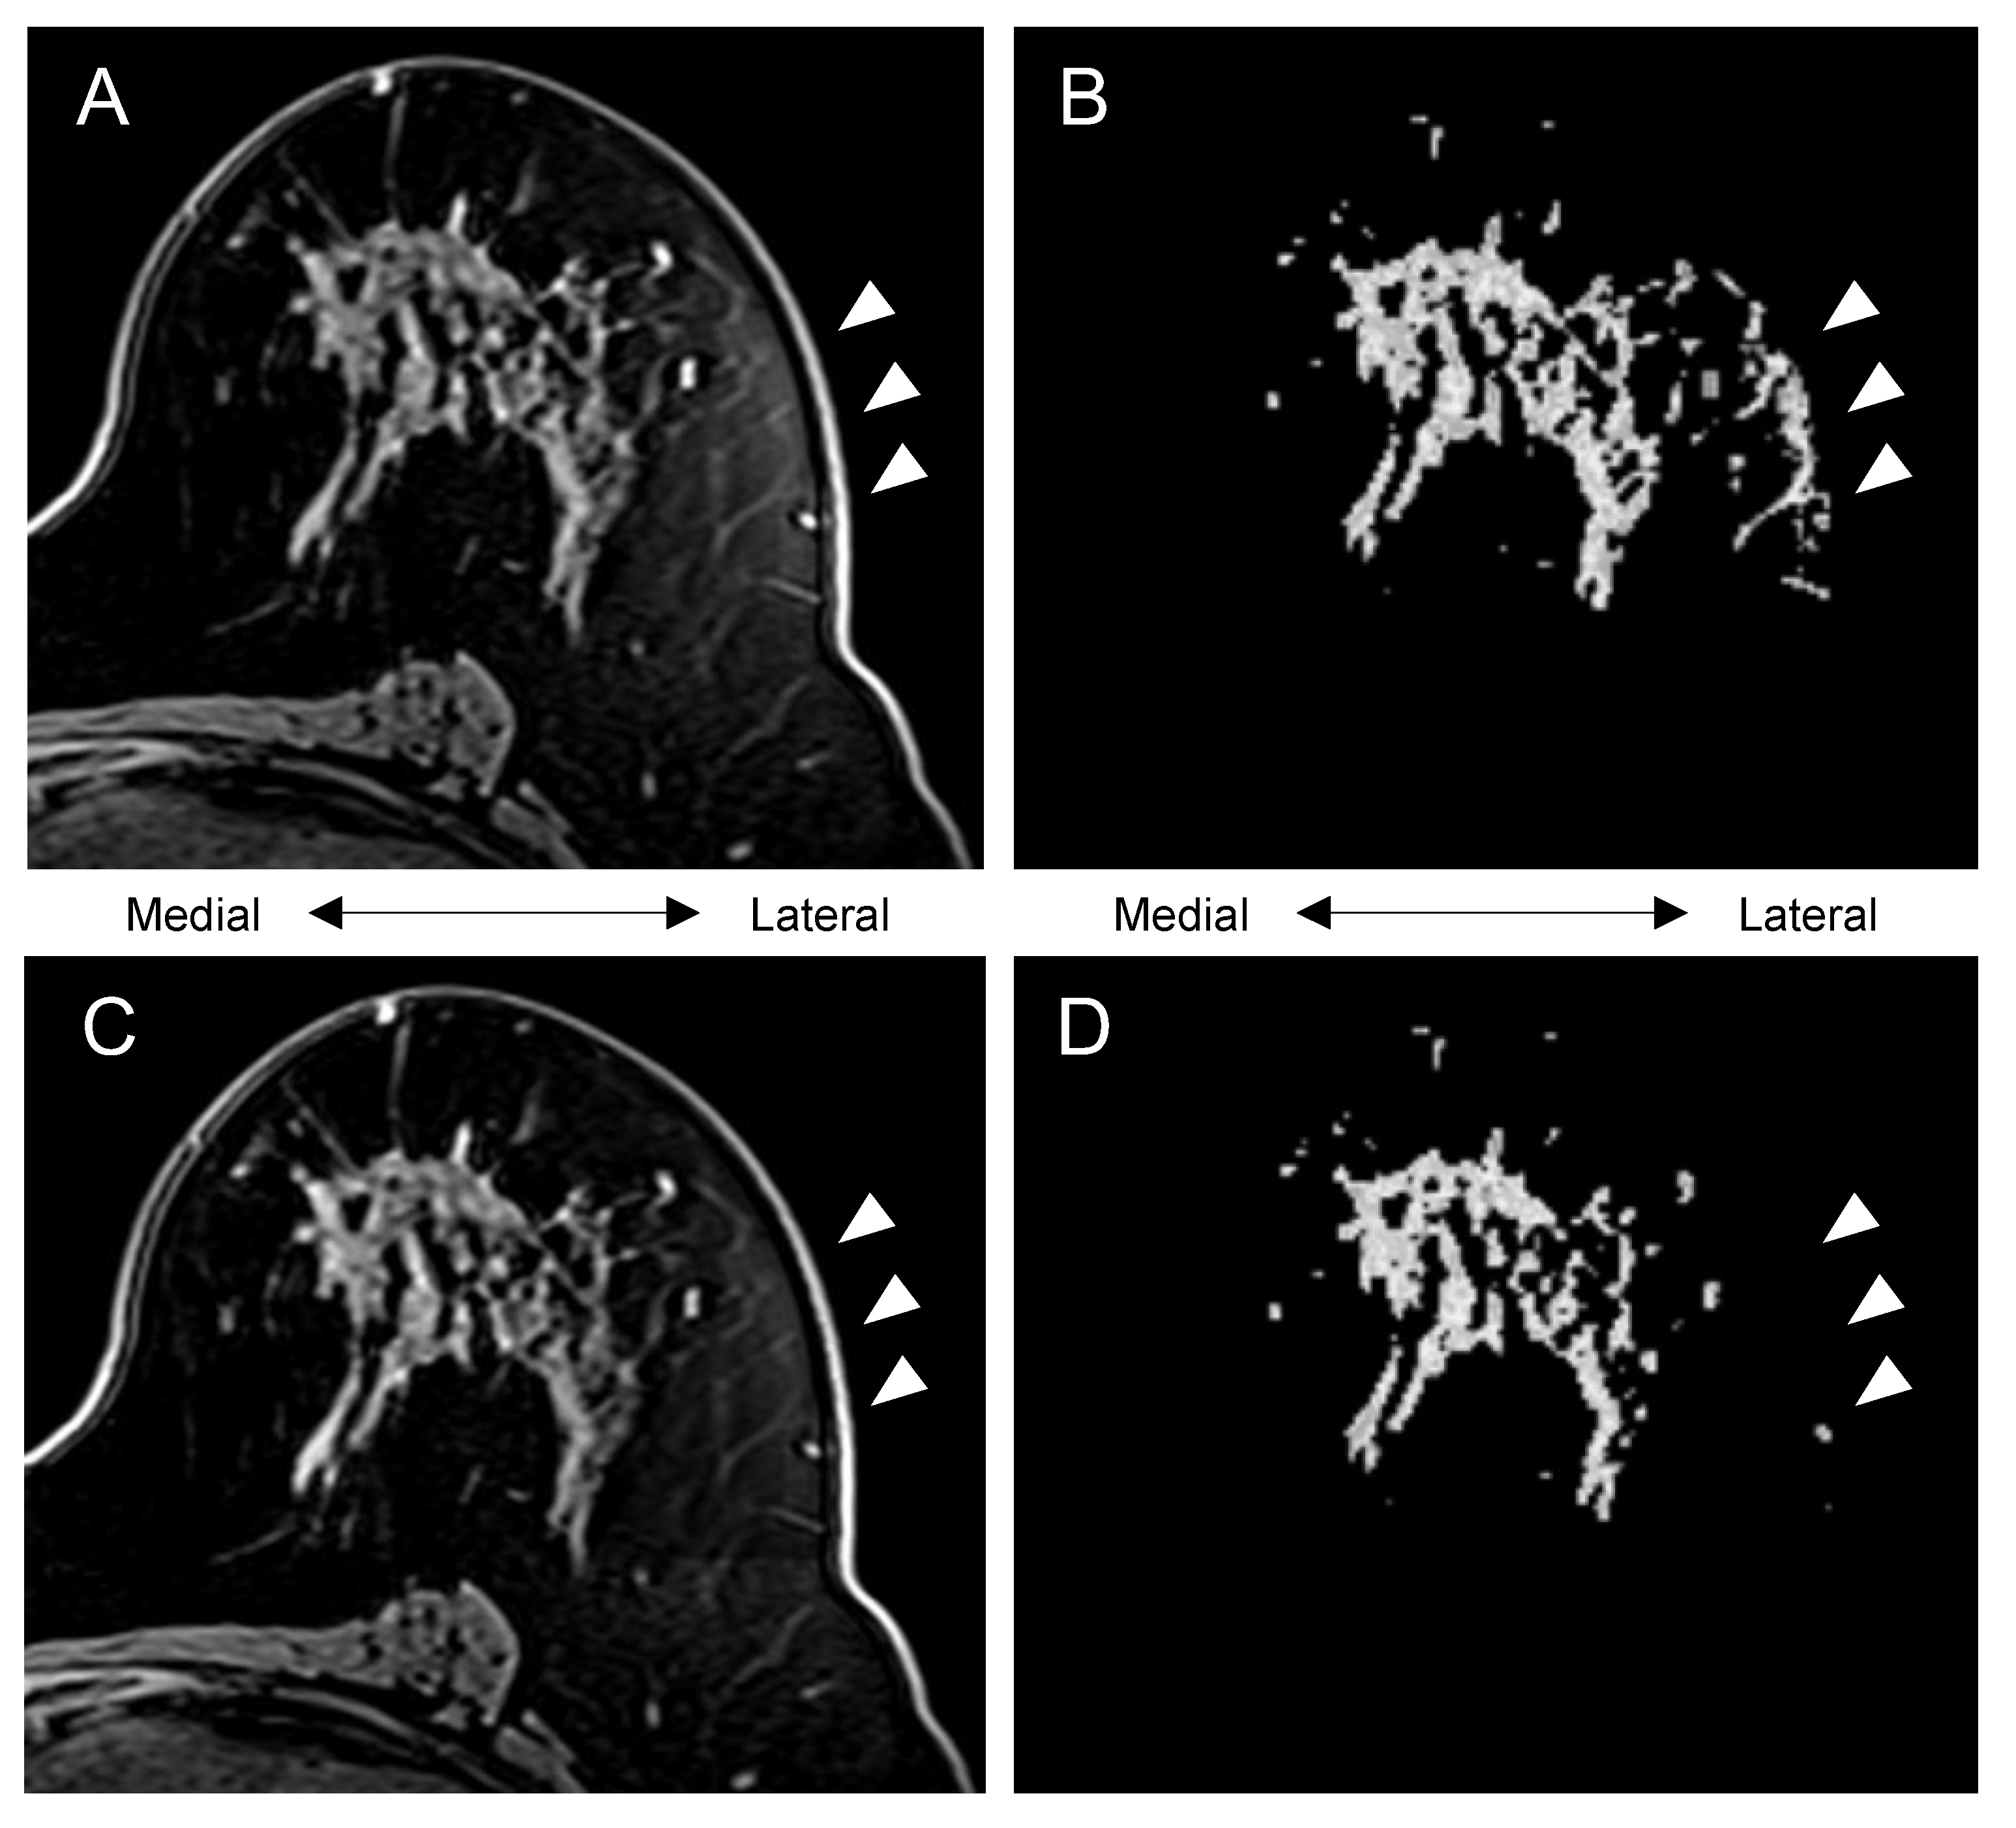

3.3. Visually Evaluated Effect of Bias Correction